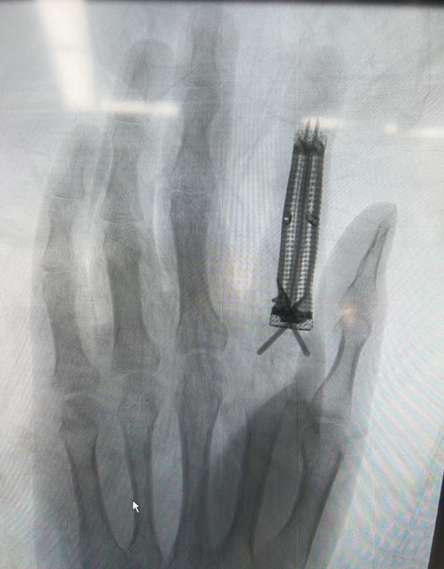

3D打印鈦合金假體,治療手指骨缺損

因手指骨腫瘤手術(shù)切除后手指骨大塊缺損,27歲的深圳市民吳先生 (化名)在南方科技大學(xué)醫(yī)院接受了3D打印鈦合金指骨假體植入術(shù),重獲一個外觀正常、功能基本正常的手指,也重獲了自信。

經(jīng)多方打聽,吳先生慕名來到南方科技大學(xué)醫(yī)院。骨科醫(yī)學(xué)部創(chuàng)傷骨科趙東升主任和3D打印醫(yī)學(xué)部副部長裴延軍認(rèn)真研究,并制定出3D打印鈦合金指骨假體解決骨缺損問題的詳細(xì)手術(shù)方案。手術(shù)要把原來的骨水泥取出,用3D打印鈦合金指骨假體代替,手術(shù)難度在于吳先生左手食指殘留的骨段非常短,不足1厘米,假體和殘留骨面的固定和愈合都不容易。

吳先生為材料學(xué)碩士,他對趙東升主任提出的手術(shù)方案高度認(rèn)同,他知道鈦合金假體非常適合做生物體植入。完善術(shù)前準(zhǔn)備后,手術(shù)由趙東升主任和鄭木平主任主刀,在全麻下進(jìn)行,歷時2小時順利完成。術(shù)后,3D打印醫(yī)學(xué)部副部長裴延軍為吳先生定制了3D打印支具進(jìn)行固定,保護(hù)手指,吳先生定期來門診復(fù)查。目前吳先生對自己的手指外形滿意,功能正在恢復(fù)中。人體骨折愈合通常需要3個月以上,3D打印假體的愈合需時可能更長,在此期間,支具的保護(hù)、適當(dāng)?shù)墓δ苠憻捄苤匾?。吳先生的手指有望獲得具有滿足日常需要的功能。